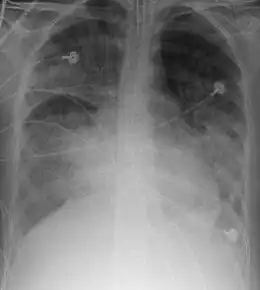

Le SDRA est défini par l'association de quatre critères : détresse respiratoire depuis moins d'une semaine, opacités pulmonaires bilatérales sur la radiographie thoracique ou la tomodensitométrie (TDM), pas d'argument pour une cause cardiaque d'œdème pulmonaire, et hypoxémie.

- opacités pulmonaires bilatérales floconneuses sur la radiographie thoracique ou la TDM, non expliquées par un épanchement, une atélectasie, ou des nodules ;